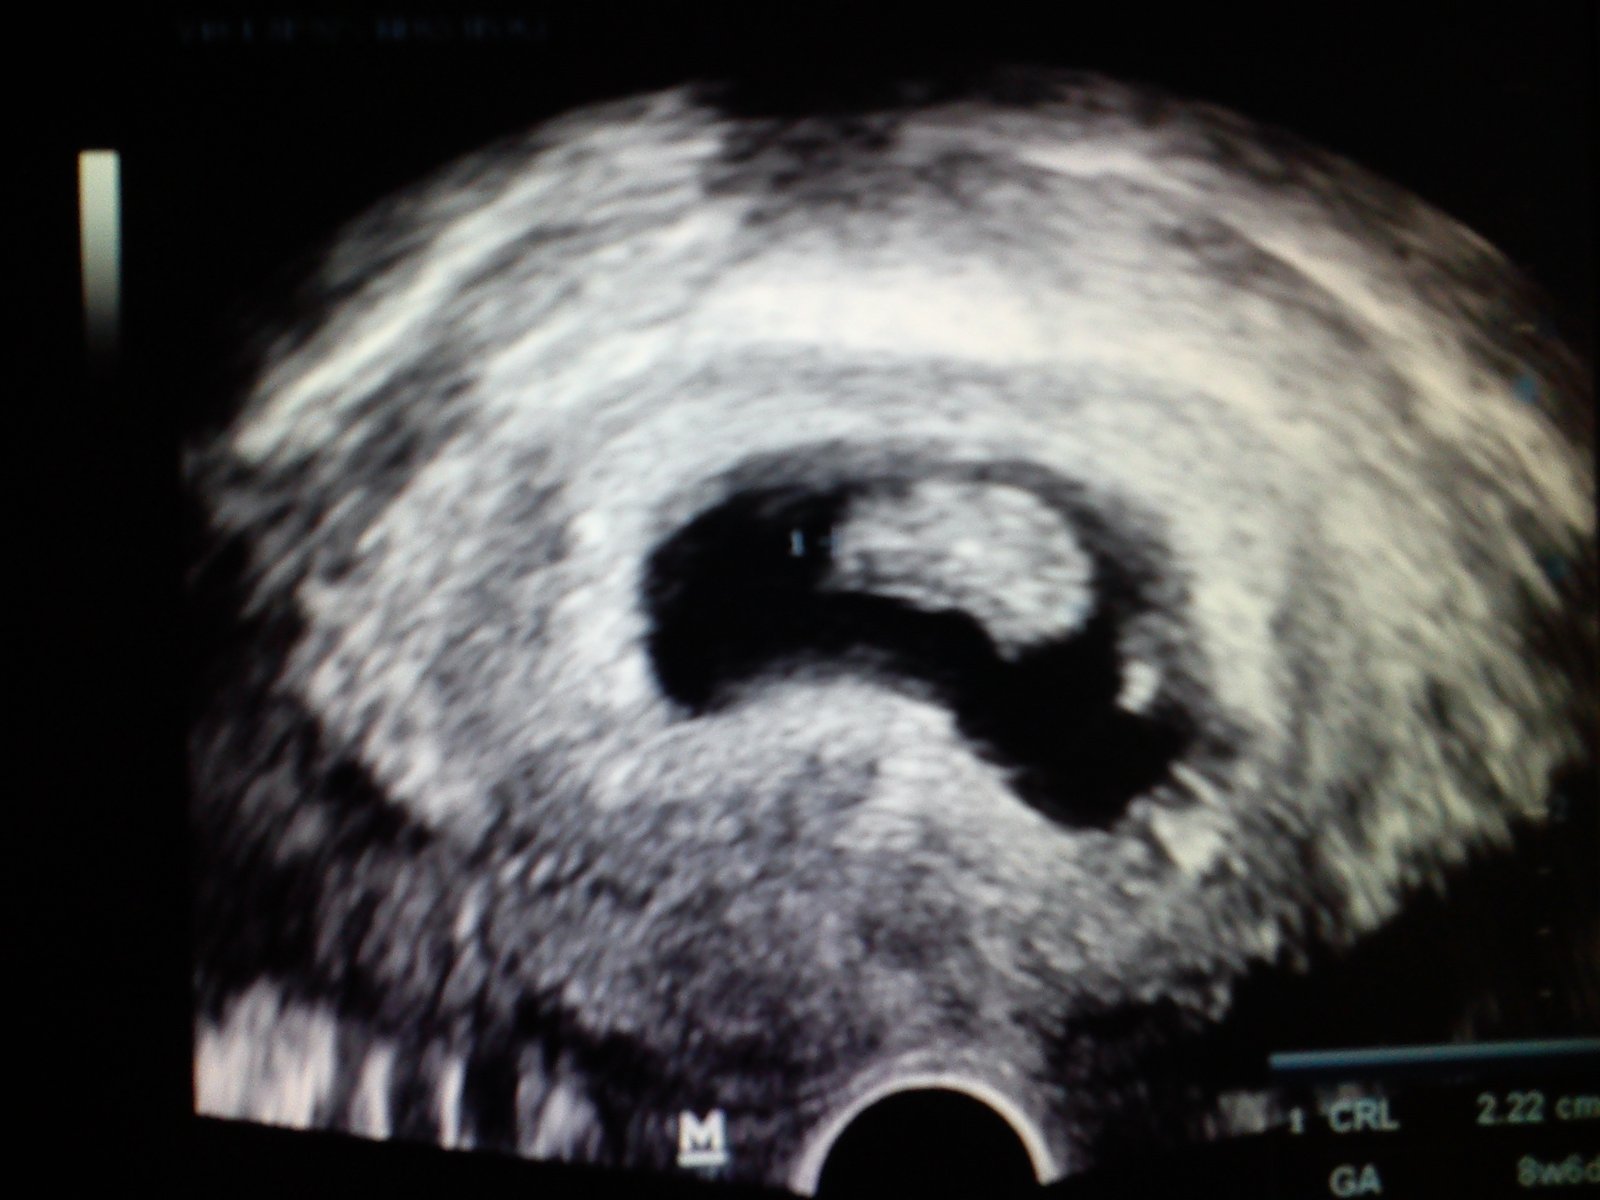

Ahojte, tak sa ozyvam po dlhsej dobe...ked mi lekar oznamil ze na ultrazvuku je to moc mini a ze nevie ci to je mimomaternice alebo sa nevie ci sa bude spravne vyvyjat...som bola uplne nestastna z toho prestala som sem nakukat ..ale dnes som bola u lekara na ultrazvuk a takato krasna fazulka sa objavila je otocena chrbatikom, srdiecko krasne bilo a ma uz 2,22cm. Este nemam tehu knizku az 29.9.idem na odbery a kontrolny ultrazvuk tak ak bude vsetko ok dostanem uz aj knizocku. Povedal ze sa mozem zacat tesit 🙂 Drzim vam vsetkym silno palceky aby ste o chvilku davali foto ultrazvukov 🙂 a drze nam prosim silno palce nech je vsetko ok stale sa bojim ale trosku sa od dnes aj tesim 🙂

@margaretkaoliver krasna fotka 🙂 gratulujem a vela stastie zelam 🙂

@margaretkaoliver gratulujem držkajte sa